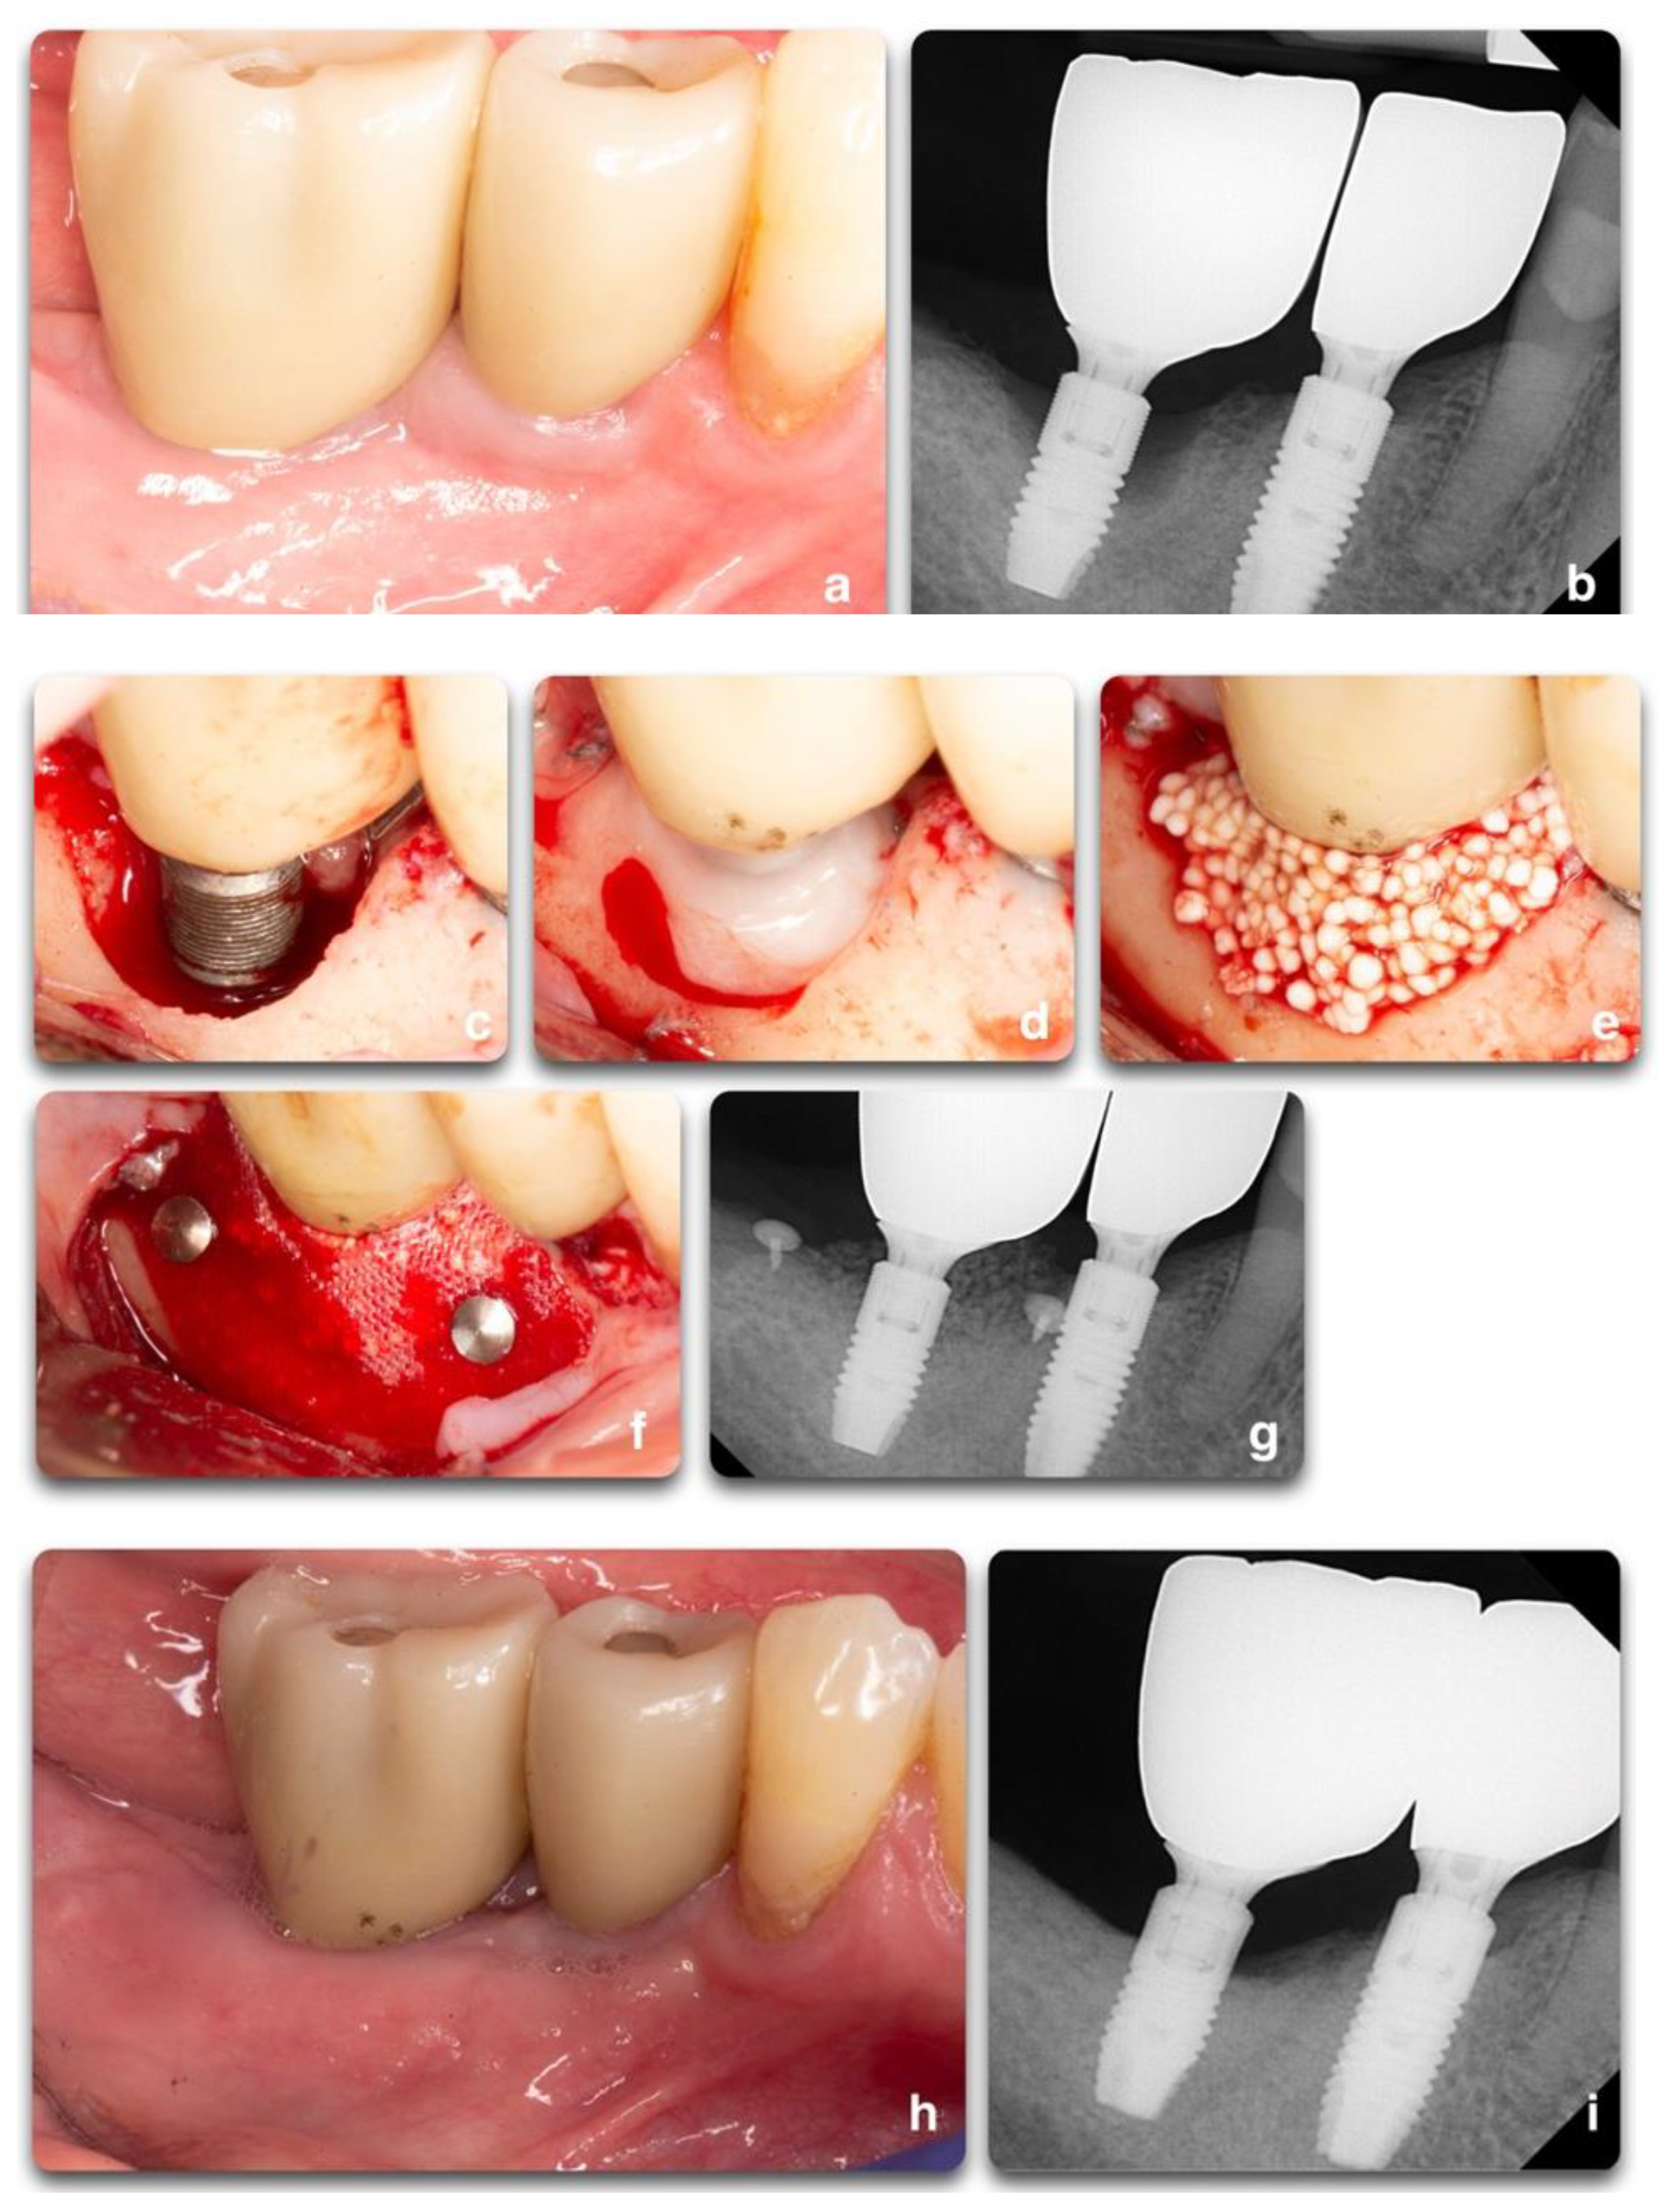

Figure 9.

Regenerative peri-implant therapy for implant area #31. (a,b) Pre-operative clinical and radiographic presentation. BoP, SUP, PD 10mm. (c) Defect configuration after the elevation of the full-thickness flap on implant #31. (d) Implant surface decontamination with rotating titanium brushes, saline and chlorhexidine rinse, and the application of PrefGel® 24% EDTA (2021 Institut Straumann AG®). (e,f) Bone grafting application (GUIDOR® easy-graft® CLASSIC Alloplastic Bone Grafting System © © Copyright Collagen Matrix, Inc.—Allendale, NJ, USA), covered by the GUIDOR® matrix barrier membrane, and stabilized by two titanium tacks. (g) Radiograph showing the grafting material at the time of surgery completion. (h,i) 13 months post-operative clinical and radiographic outcomes. Partial fill of the intra-bony defect with a residual supra-crestal defect.